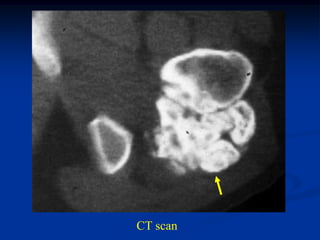

Case #625.1                 Multiple hereditary exostoses

50 yr old female with short stature and R hip pain for years

AP and lateral of right hip

AP and lat tibia

Proximal humeral x-rays

AP and lateral of femur

Lateral ankle

Oblique foot